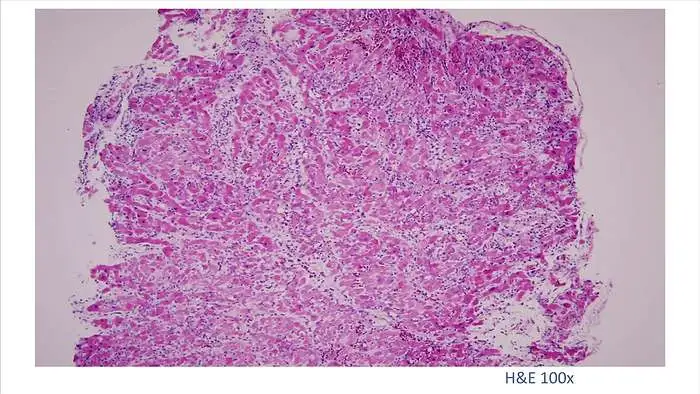

6.

这是她的心肌病理切片,放大了100倍。

7.

100倍还不是看得很清楚,放大400倍就很明显了,一个个蓝点就是淋巴球。这是很厉害的猛暴性心肌炎,整个心脏都被淋巴球浸润了。